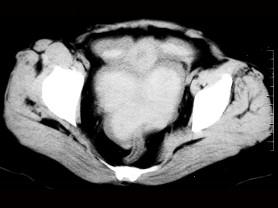

问题 女 ,32岁 ,因停经46天 ,少许不规则阴道流血15天 ,下腹胀痛 3 天入院,后穹窿穿剌抽出不凝血,CT检查如图所示,下列说法错误的是 ( )

选项 A、此为宫外孕 B、此为卵巢巧克力囊肿 C、病灶外缘较光整 D、盆腔内较高密度积液 E、在左附件区可见一椭圆形略高密度病灶

答案 B